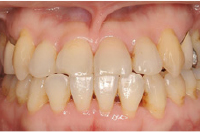

治療後